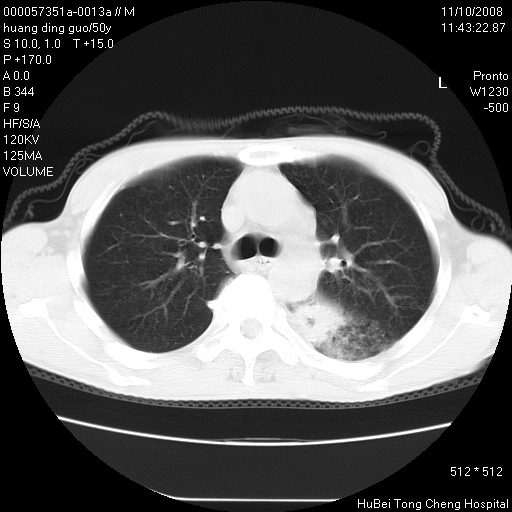

患者 男,50岁。左侧腰背部疼痛3月余,伴消瘦。平素健康,无传染病史。

胸部ct轴位平扫(层厚10mm,螺距1.5,重建间隔10mm),图像如下:

左肺下叶背段有一厚壁空洞,外壁呈锯齿状伴毛刺改变。空洞相邻胸膜有牵拉改变。左肺下叶血管支气管束不规则增粗,小叶间隔增厚。胸椎骨质破坏。考虑左肺下叶周围型肺癌伴左肺下叶癌性淋巴管炎、胸椎转移。

左肺下叶背段有一厚壁空洞,外壁呈锯齿状伴毛刺改变。空洞相邻胸膜有牵拉改变。左肺下叶血管支气管束不规则增粗,小叶间隔增厚。胸椎骨质破坏。考虑左肺下叶周围型肺癌伴阻塞性肺炎、胸椎转移。其他待排

左肺下叶背段有一厚壁空洞,内壁不规则,外壁呈锯齿状伴毛刺改变。空洞相邻胸膜有牵拉改变。周围呈絮状炎性改变,左肺下叶血管支气管束不规则增粗,小叶间隔增厚。胸椎骨质破坏。考虑左肺下叶周围型肺癌伴左肺下叶阻塞性肺炎、胸椎转移。